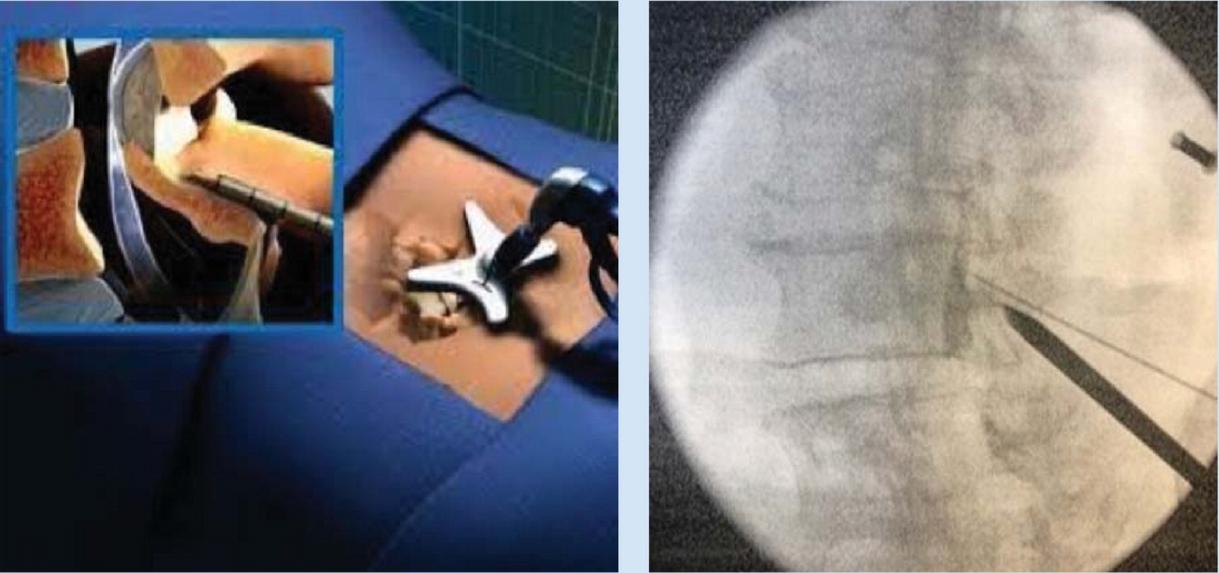

KYPHOPLASTY AND VERTEBROPLASTY

VERTEBROPLASTY

Steps

1. OperativeLevelIdentification:Identifytheoperative levelusingfluoroscopy.

PatientPositioning:Prone(thoracolumbar)forneedle placementfromeithersideandeasierpositioningofCarm Cushionstosupportheadandbody Adedicated biplanefluoroscopysuiteispreferred,butatleastone C-armunitisnecessary

Needleplacement:

Transpedicular:needlethroughfulllengthofpedicle a

Parapedicular:needlealongthelateralcortexof pedicle b

TrajectorySafetyConsiderations

APviewsafetyconsiderations;(a)keeptomedialborderof pedicleinordertoavoidspinalcord/thecalsac,(b)don’t strayawayfromwithinpedicularborders,thiswillensure safetyofnervesandnerveroots lateralviewsafetyconsiderations;(a)cannulatipshouldbe seenattheposteriorbodywallinthelateralview,(b)the aorta/inferiorvenacavacanbedamagediftheanterior vertebralbodyispenetrated,(c)penetratingtheinferior pediclewallasaresultofimpropertrajectorycancause nervedamage

Image-guidancestrategiesforatranspedicular approach:

a

b

Endontechnique:asdescribedbelowinthe kyphoplastyproceduredescription

APtechnique:craniocaudalangulationisadjusted sothattheendplatesareperpendiculartothe image.

i

Skinentrypoint1cmsuperolateraltopedicle’s centre,needleisadvancedanteriorly,medially andcaudally

iii

Needletipshouldinitiallyprojectovertheupper outercortexofthepedicle,needleisadvanced sotipprojectsovercentreofpedicleonAPand lateralviews

ii tipshouldbeoverthemedialpediclecortexas theneedlemovesacrosstheposteriorthirdof thevertebralbody.

Image-guidanceforaparapedicularapproach: Needleplacementissuperolateraltolateralpedicular cortex,entersthevertebralbodyatthejunctionofthe pedicleandvertebralbody

5. Cementplacement:fluoroscopicmonitoringis importanttoensurecementremainswithintheareaof target Lateralviewsaremoreimportantasitenables theevaluationoftheposteriorpositionofcement relativetospinalcanalandneuralforamina

6. ProcedureCompletion:postprocedureradiographsare takenandpatientismonitoredfor1-2hoursafter, includingneurologicassessment

AdditionalPoints

Needleshouldnotviolatethemedialcortexof pedicle

Trajectoryofneedlecannotbealteredmuchonce needlehaspassedintothepedicle

Avoidcannulacrossingmedialpedicularborder priorreachingposteriorwall(redline,Figure9A)to ensuresafetyandevendistributionofcement

Figure13:Illustrationsof vertebroplasty.

A)Preoperativeplanningofentry pointsandtrajectory(yellow: bipedicularapproach;purple: unipedicularapproach;red:medial pedicularborder),

B)Simplifiedschematicsof relevantanatomicallandmarks andangulation

C)Approximatetrajectory, D)Lateralfluoroscopicviewof cementinjection